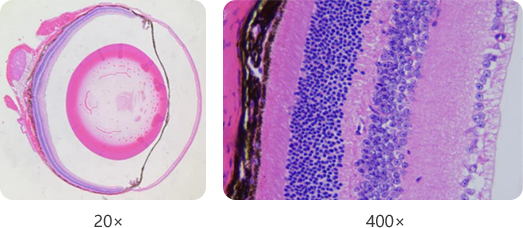

小动物眼科病理学分析

小动物眼科结构和大动物存在结构上的差别,赛业针对小动物眼科病理检测多重难点进行了攻关,建立了一套切实有效的病理检测方法。

● 图左:小鼠眼球HE染色(石蜡切片);图右:视网膜HE染色(石蜡切片)